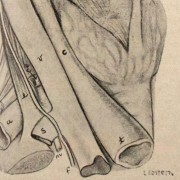

Lilly Ebstein Lowenstein (1897-1966) led a life between science and art, drawing and taking photographs in the fields of Medicine and Zoology. In her work, Lilly combined her technical knowledge of photography and drawing, the study of the sciences and a remarkable talent for aesthetics. She was born in Germany and studied at the Lette-Verein School in Berlin from 1911 to 1914. In 1925, she immigrated with her husband and two children to São Paulo. In 1926, she became an illustrator and photomicrographer at the Illustration and Photography Department at the School of Medicine (USP, as of 1934), which she headed for thirty years after 1932. Lilly collaborated at Instituto Biológico de Defesa Agrícola e Animal (the Biological Institute for the Defense of Agriculture and Animals), from 1930 to 1935, namely in the Avian Pathology Department. A life with art dedicated to the research and dissemination of science.